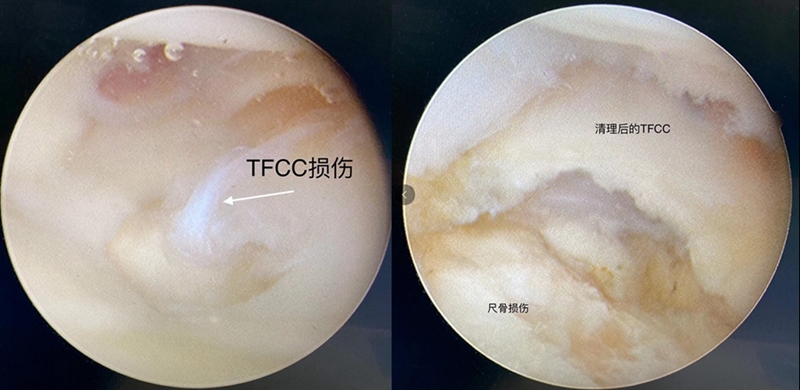

Case1

女性,42岁,右腕疼痛1年+,2020年4月手术。

影像学检查

关节镜视频

关节镜下清理后